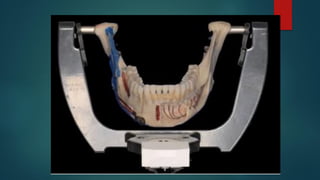

Figure 13-4 A, The trimmed dental casts

are then mounted on the semi-adjustable

articulator with the use of the face-bow

apparatus. The temporal arms of the face

bow are maintained parallel to the upper

aspect of the articulator and the counter

top. Base plates for the maxillary and

mandibular units are secured to the

articulation. A bite-fork support is useful to

prevent the sagging of the face-bow

apparatus when mounting the maxillary

cast. B, The plaster is mixed and added

in between the maxillary dental cast and

the base plate. C, With the maxillary unit

initially set (≈15 min), the articulator is

turned upside down.

The centric relation wax bite is occluded

to the maxillary cast. The trimmed

mandibular cast is then occluded to the

other side of the wax bite.